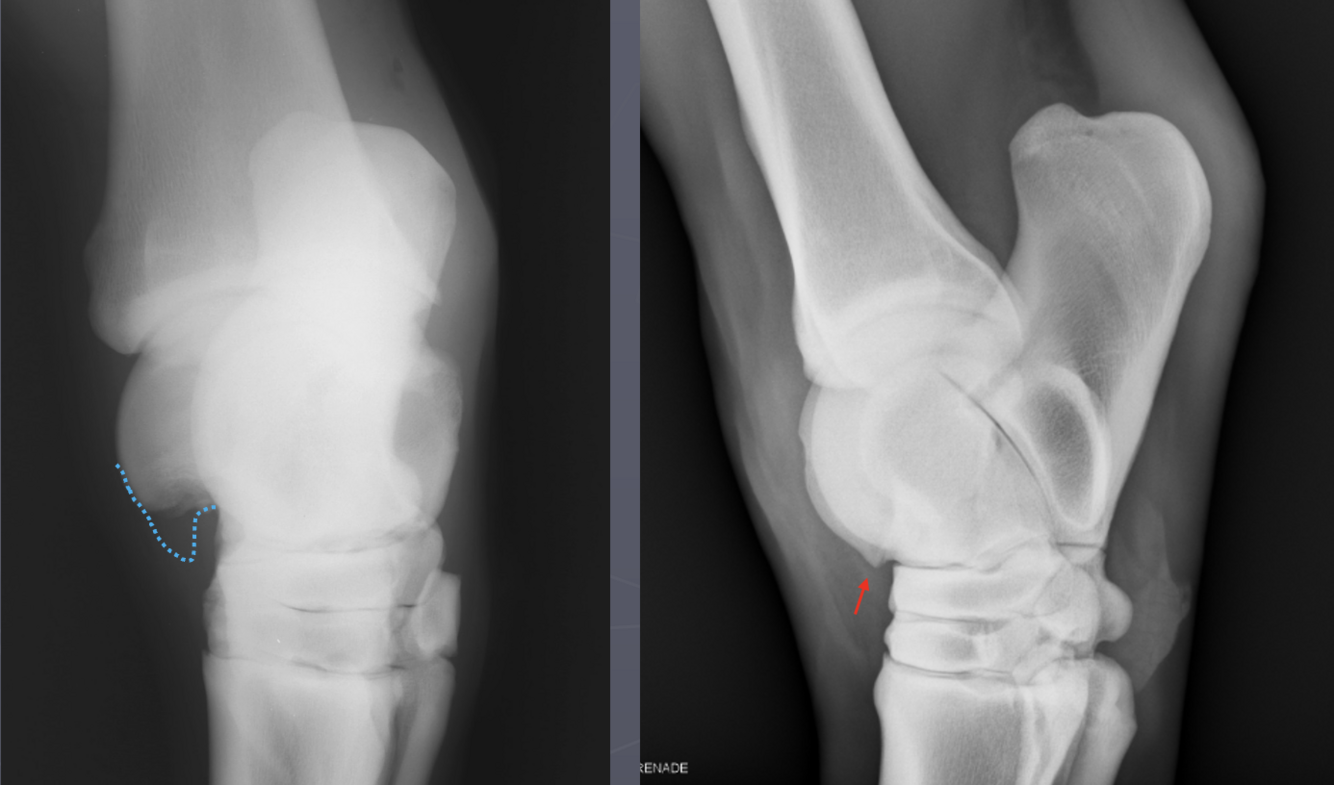

What is shown in these images?

Left: osteochondrosis of lateral trochlear ridge of talus

-“missing” bone that is cartilaginous instead of mineralized

Right: osteochondrosis of lateral trochlear ridge of talus

-lesion is the divot seen on lateral trochlear ridge

-red arrow is pointing to normal variation of the medial trochlear ridge